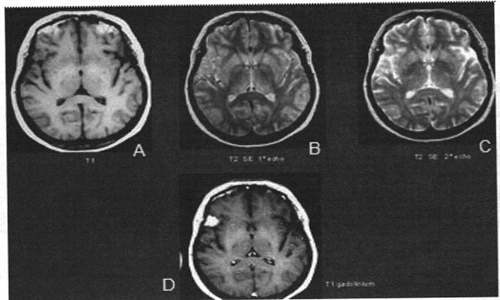

Chẩn đoán thần kinh qua hình ảnh chụp cộng hưởng từ não

Phát hiện khối u não qua hình ảnh MRI